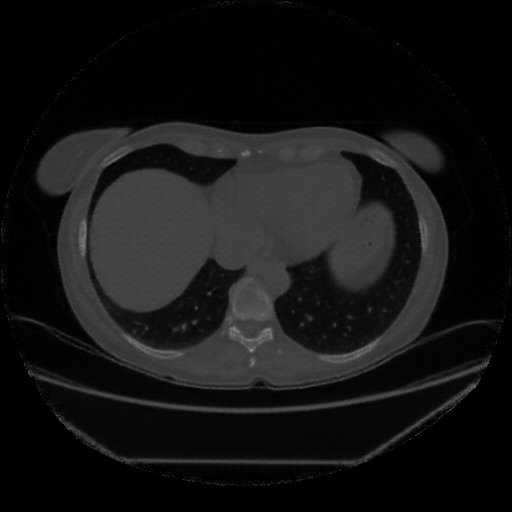

Image Grid

4Γ—3 grid: Rows show different image types (Original NATIVE, Reconstructed NATIVE, Original VENOUS, Generated VENOUS), Columns show windowing techniques (No Window, Lung Window, Mediastinum Window)

Generated VENOUS CT scan (A→B translation)

Full window (WL 1023.5, WW 4095 β†’ Low βˆ’1024, High +3071)